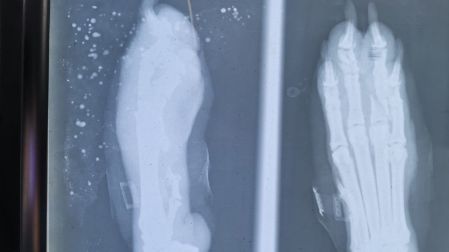

Dos proyectiles se alojaron en su abdomen y una de sus patas.

Debido a la gravedad de la herida, el perro tuvo que ser intervenido de manera inmediata logrando retirarle el proyectil.